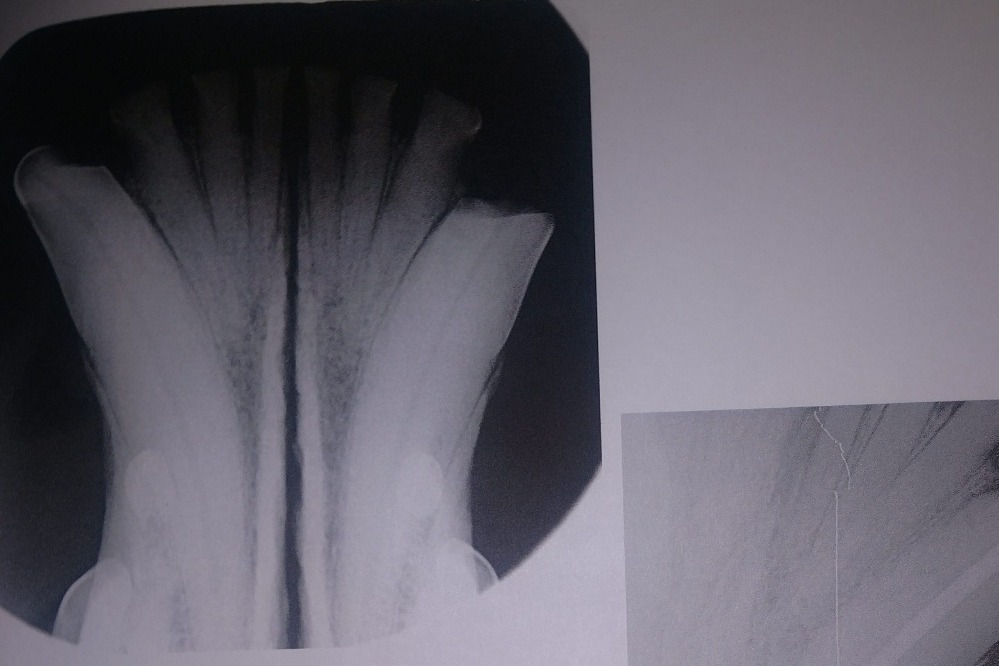

The radiographs laid out a dim story of that long term damage: all 4 canine teeth were dead, 2 of those canines were broken off from the recent attempt on the gate; all of her lower incisors, and several molars on each side were also dead. The vet was surprised, in spite of massively evident wear and tear, that her upper incisors appeared to still be alive. More of her teeth were dead than live. However, there was some good news in that her gums were completely free of gum disease, she had very little plaque and tartar buildup, and that she hadn't lost any of the bone her teeth were seated in.

So I chose the slightly worse broken canine (bottom left) and it's upper companion to get root canals that day. The upper right broken canine, in the photo above, would be much easier for me to see to monitor its condition while we saved up for more surgeries. That surgery, including the consultation, radiographs, and blood tests, came out to a total of $2,867.82.

AFTER PHOTOS: (left upper and lower canine root canals, cleaning)

The following photos are her radiographs for anyone that knows how to read them, so you can see all the dead teeth that need future extractions, and some show the root canals: